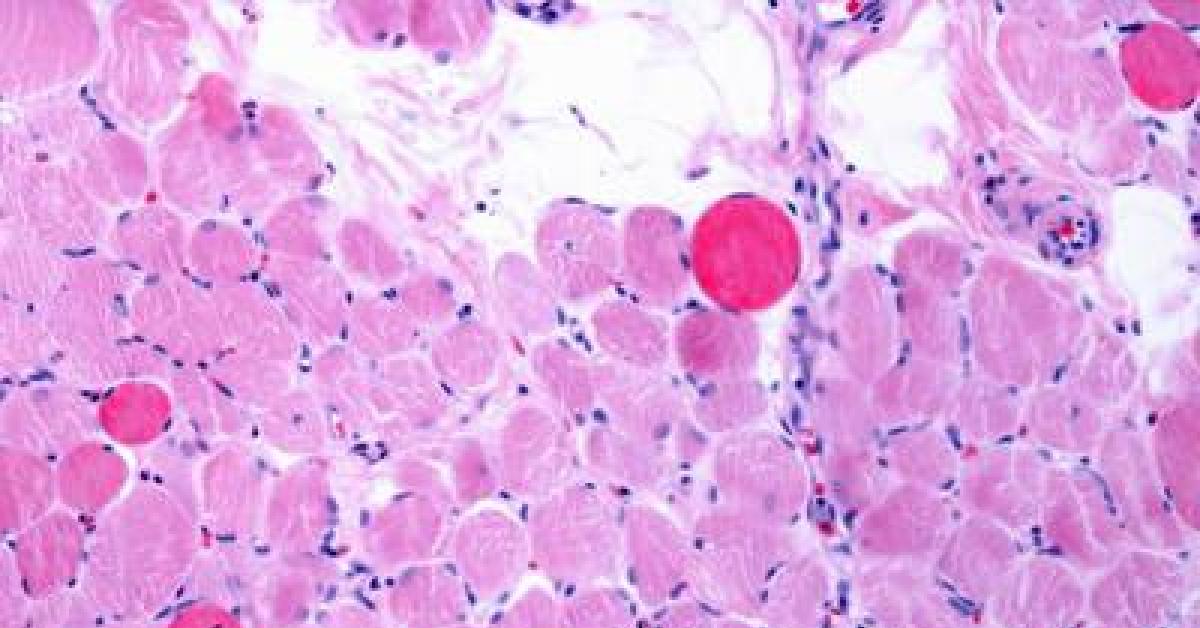

Roma, 4 nov. (Adnkronos Salute) - Sono positivi i risultati di un'analisi dei dati a lungo termine - comprese le prime valutazioni dello studio multicentrico in aperto Guardian, attualmente in corso - che valuta Agamree* (vamorolone) in pazienti affetti da distrofia muscolare di Duchenne (Dmd). Lo annuncia in una nota Santhera Pharmaceuticals, precisando che l'analisi ha incluso pazienti mai trattati con corticosteroidi e che hanno iniziato il trattamento con Agamree tra i 4 e i 7 anni di età nell'ambito di studi clinici, proseguendo poi attraverso vari programmi di accesso tra cui lo studio Guardian.

Sono stati analizzati i dati di un massimo di 110 pazienti, con un numero variabile in base alla disponibilità delle informazioni. In questa analisi i pazienti avevano ricevuto il trattamento per un massimo di 8 anni, con un follow-up mediano di circa 5 anni. La maggior parte dei pazienti ha mantenuto dosi elevate (4-6 mg/kg/giorno) in contesti clinici di real world durante il periodo di osservazione. I risultati mostrano che i pazienti trattati con vamorolone hanno mantenuto la funzione motoria durante il follow-up prolungato, dimostrando un'efficacia duratura del trattamento misurata in base al tempo di perdita della deambulazione paragonabile a quella dei corticosteroidi standard (p=0,91). Nelle analisi di sottogruppi prestabilite non sono state osservate differenze rispetto al deflazacort o al prednisone assunti quotidianamente. I dati - riporta l'azienda - continuano a confermare un profilo di sicurezza e tollerabilità differenziato rispetto ai corticosteroidi tradizionali. I pazienti trattati con Agamree hanno registrato un tasso significativamente inferiore di fratture vertebrali (p=0,0061), hanno mantenuto una crescita normale senza il rallentamento osservato con i corticosteroidi standard (p<0,0001) e hanno mostrato un numero inferiore di casi di cataratta rispetto ai pazienti trattati con glucocorticoidi, compresa un'incidenza notevolmente inferiore rispetto ai pazienti trattati con deflazacort (p<0,015). Inoltre, a oggi, non sono stati osservati casi di glaucoma. In media, le variazioni dell'indice di massa corporea o del peso, se rapportate all'altezza, non hanno mostrato differenze e non sono stati osservati nuovi segnali di sicurezza.